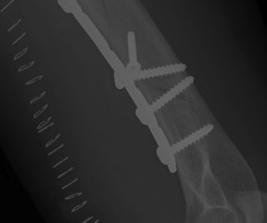

1. Lag screws

Lag Screws

Stability is achieved by compression and bone contact

- load transfer occurs directly from fragment to fragment and not via the implant

- should be placed perpendicular to the fracture line

- can apply 2000-4000N

- 1 screw is never strong enough to achieve stable fixation and 2 or 3 screws are required

- provide excellent stability but their strength is usually inadequate to resist displacement under functional loads

- are therefore usually combined with a neutralisation plate

Plates

1. Neutralisation plate

Neutralisation plate

- used to protect lag screws

- conduct part or all of the force from one fragment to another

- protect the fracture fixation from bending, shear, and rotation

- e.g. lateral malleolus fractures - lag then apply a derotation plate